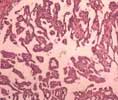

②透明細胞癌:癌細胞胞漿透明,呈低柱狀或立方形,其間散在一些基底部狹窄,頂端肥碩,胞漿稀少,核大深染的鞋釘細胞,細胞排列成實性團塊、條索狀或乳頭狀。

陰道透明細胞腺癌,一般生長部位較淺,可累及陰道任何部分,但最常見部位為陰道上部前壁,同陰道腺病。病變局限於黏膜層或只有很淺的肌層浸潤,多數呈息肉狀,有的呈結節狀、扁平斑或潰瘍形。鏡檢:癌細胞胞漿透亮,細胞排列呈腺管囊狀、乳頭狀或實體狀,以第一種為主。細胞呈鞋釘狀,胞漿不含粘液,核為球形,突入腺管腔內,有時酷似子宮內膜腺癌(類子宮內膜癌)。特殊染色時顯PAS強陽性。電鏡觀察,可見透亮的細胞中含有很多糖原,有短而粗的微絨毛,溶酶體及脂滴較少,內質網呈平行排列。